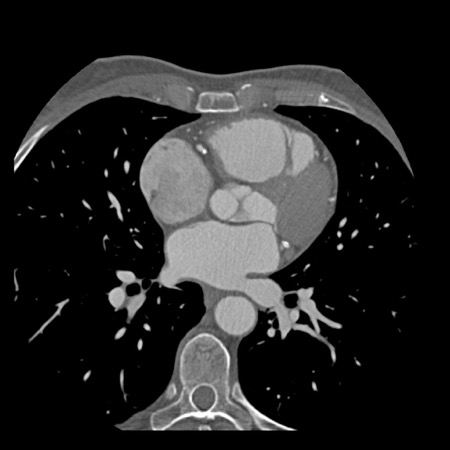

Modifier S – stent

The presence of a stent is indicated by modifier “S”.

Examples

- If a patient has a stent, showing no in-stent restenosis and a mild

(25-49%) stenosis in the coronaries, this patient classifies as CAD-RADS

2/S. - Similarly, a patient with no in-stent restenosis but severe (70-99%)

stenosis in a coronary other than LM classifies as CAD-RADS 4A/S. - If there is a severe (70-99%) in-stent restenosis in a coronary other

than LM, this patient classifies as CAD-RADS 4A/S. - If the stent is non-diagnostic and there is no >49% stenosis present

in the coronaries, the patient classifies as CAD-RADS N/S.

Note: the location of the stenosis does not matter, when using

CAD-RADS.

What matters is that the patient has a severe stenosis and needs further

management.

Please note: total coronary plaque burden should also be added and is

placed before the modifier S.